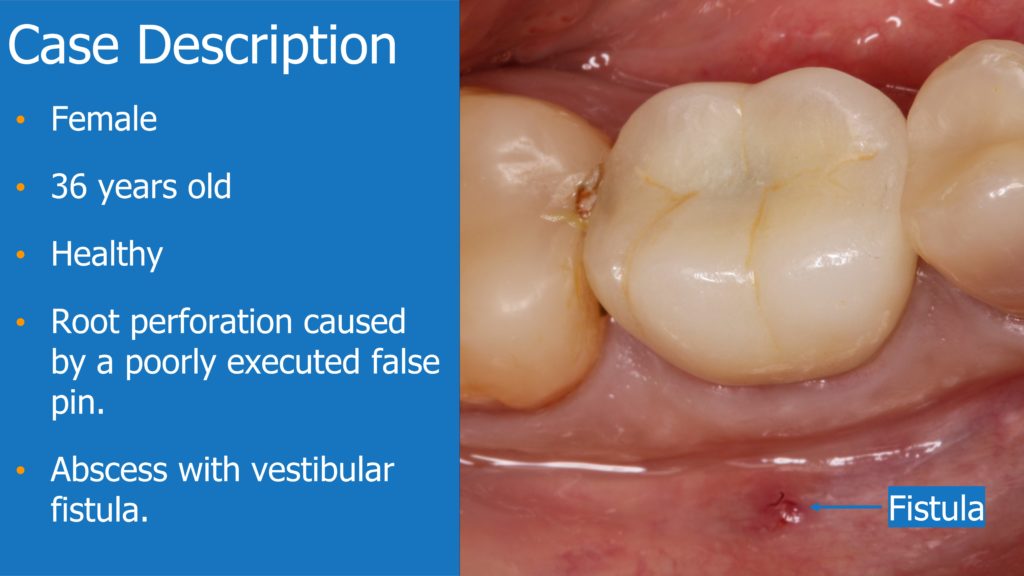

A healthy 36 year old woman comes to the clinic with pain and swelling in the area of the inferior left molars. In the intraoral observation, a vestibular fistula was identified, and the complementary exams confirmed a bone lesion caused by a root perforation (poorly executed false post) on the first lower left molar #36 (19). It was decided to do antibiotic therapy for a week and then the tooth extraction with immediate implant placement and bone graft. 4 months post-op the definitive zirconia/ceramic crown would be was made.